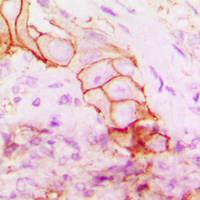

Immunohistochemical analysis of CD104 staining in human breast cancer formalin fixed paraffin embedded tissue section. The section was pre-treated using heat mediated antigen retrieval with sodium citrate buffer (pH 6.0). The section was then incubated with the antibody at room temperature and detected using an HRP conjugated compact polymer system. DAB was used as the chromogen. The section was then counterstained with haematoxylin and mounted with DPX.